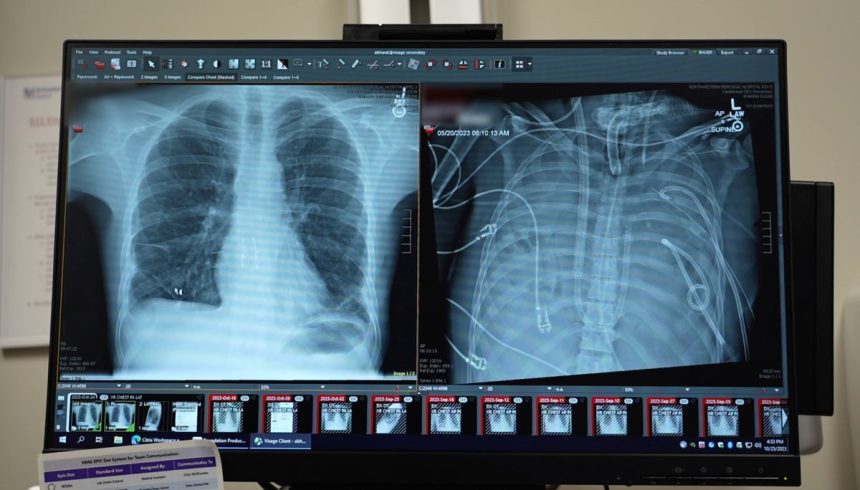

The patient required a double-lung transplant to survive, but he was too sick for the procedure. Without functioning lungs, he would not survive. Although he was on extracorporeal membrane oxygenation (ECMO) to assist with breathing, this treatment was ineffective without lungs. Bharat devised a plan to create artificial lungs that could oxygenate the blood and keep the patient alive long enough to receive a transplant.

The artificial lungs acted as a bridge, allowing blood to be pumped from the right side of the heart to the left side, where it could be oxygenated and circulated throughout the body. This innovative system kept the patient alive for two days, giving him a chance to recover from the infection. Eventually, the patient was placed on the lung transplant list and received new lungs, leading to his eventual discharge from the hospital.